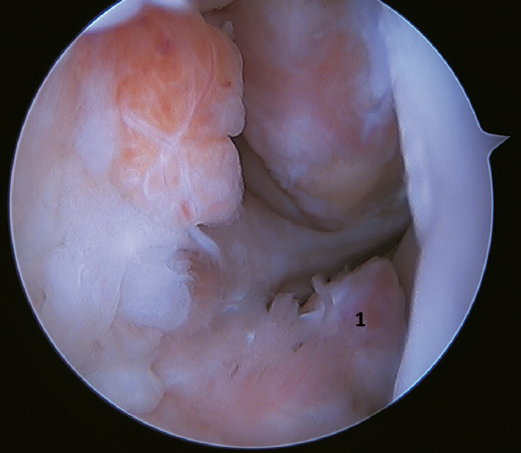

Another point of interest is the presence of os subfibulare. In these cases, we have the option of fixation, although this is usually not feasible and the best therapeutic option is excision and reconstruction, due to the impossibility of direct repair(60)(Figure 4).